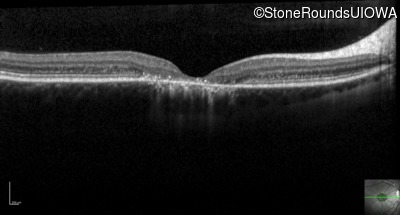

Optical Coherence Tomography - Right - 20/125 sc

Exemplar / OCT Stack

OCT Stack